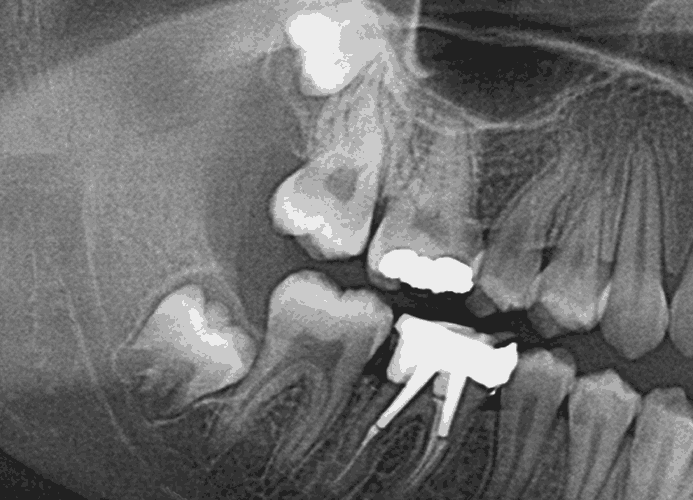

매복 사랑니 발치를 부주의하게 진행할 경우 신경손상, 상악동천공 등의 부작용이 생길 수 있습니다. 청담뷰는 사전에 파라노마 방사선과 3D-CT(컴퓨터단층촬영)검진을 통해 신경손상 없이 안전하게 발치해 드리며 최소한의 통증으로 안전하고 신속하게 사랑니 수술을 받을 수 있습니다.

사랑니 발치는 정확한 진단과 위치 파악이 중요합니다.

사랑니 발치의 정확한 진단과 발치를 위해 CT촬영을 통한 정밀 진단 후 수술을 받는 것이 안전합니다.